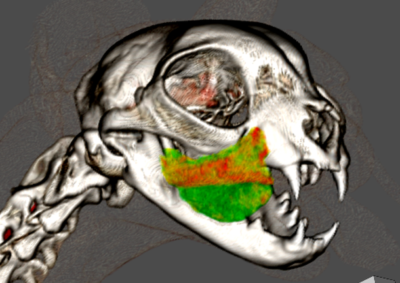

腫瘍外科 注意 ボタンをクリックした先に、治療中および手術中の画像が説明で使用されている場合がございます。 そのような画像に弱い方は閲覧なさらないようお願いいたします。 腫瘍外科 フレンチブルドッグ胃腺癌 胃部分切除 軟部組織外科腫瘍外科救急・集… 肝臓腫瘤破裂による腹腔内出血 腫瘍外科腫瘍内科 猫の直腸切除吻合 直腸リンパ腫 腫瘍外科 犬の肺腺癌の1例 腫瘍外科放射線治療 犬の軟部組織肉腫に対する腫瘍辺縁切除及び術後放射線療法 腫瘍外科 犬の肝細胞癌 軟部組織外科腫瘍外科 ジャックラッセルテリアの胃腫瘍 腫瘍外科 吻側下顎骨切除術〜メラノーマ〜 腫瘍外科 猫の上顎腫瘍切除 腫瘍外科 犬の脾臓腫瘤摘出 軟部組織外科腫瘍外科 大腸腺癌 軟部組織外科腫瘍外科 肺葉切除術 <1234567> 症例カテゴリー 放射線治療整形外科軟部組織外科脳神経外科内科腫瘍外科救急・集中治療リハビリテーション科腫瘍内科内視鏡科脳神経科呼吸器外科中医・漢方猫の腎移植循環器科